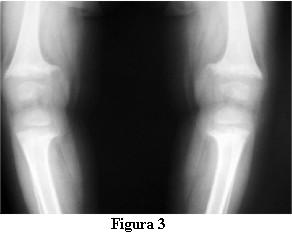

Las radiografías óseas mostraron una descalcificación global, los huesos largos incurvados y ensanchamiento de las metáfisis de los mismos en forma de copa (figuras 2 y 3).

En la evolución a los 3 meses de iniciado el tratamiento con calcitriol, a los 2 años y 9 meses, la marcha tiene las dificultades derivadas de las deformaciones de los miembros pero no presenta caídas, ni fatigabilidad, ni sudoración. La talla es de 81 cm , por debajo del percentil 3. La velocidad del crecimiento de los últimos 3 meses es de 8 cm/año. La fontanela anterior está completamente cerrada.Las radiografías óseas (figuras 4 y 5) muestran, a pesar del corto tiempo de evolución, una disminución del signo de la copa, con un progreso de la diáfisis hacia el tejido osteoide.